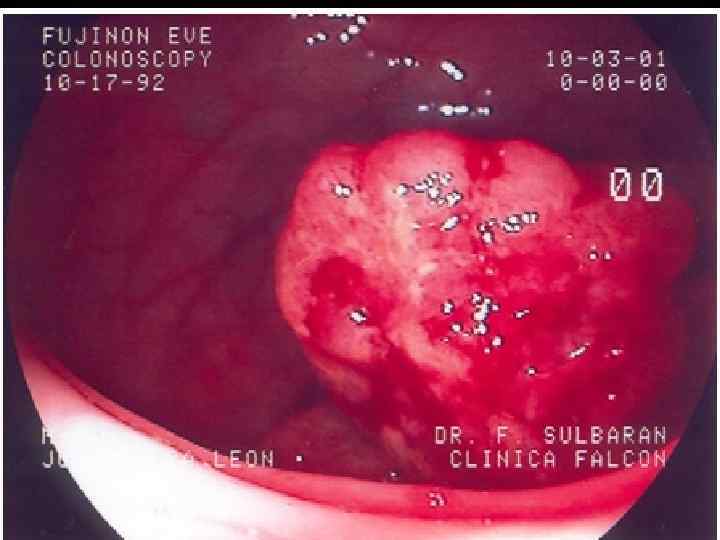

КОЛОНОФИБРОСКОПИЯ Малигнизированный полип Аденокарцинома Плоскоклеточный рак Саркома Капоши